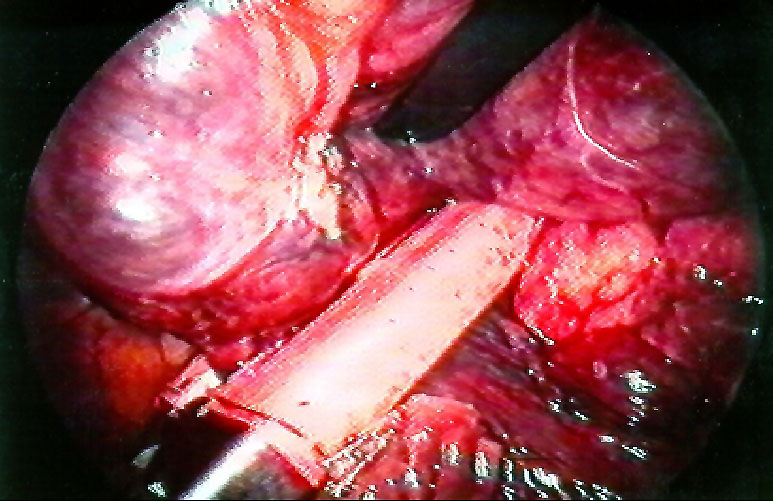

VATS bullectomy is performed under general anesthesia with double lumen endotracheal intubation. After discontinuing ventilation to the operated side, the first incision is usually made at the level of the 6th or 7th intercostal space in the midaxillary line. Careful inspection of the bulla and underlying lung parenchyma may be difficult since large bullae are usually under tension and obliterate the pleural space. The other two incisions are performed to achieve a "triangulation approach" and are used to place graspers and staplers. Pleural adhesions are coagulated and divided to completely mobilize the lung and bulla/bullae. The use of a thoracoscope with a working channel may further help to have an additional port available for instruments. The bulla can be incised and deflated to facilitate gentle manipulation of the lung; it is usually squeezed and twisted ("spaghetti procedure") to identify the base. Traction on the surrounding parenchyma must be carefully performed to avoid injuring the lung surface with consequent prolonged air leaks during the postoperative period. Pedunculated bullae are easily excised with endostapling devices. Broad-based bullae can be removed with multiple applications of endoscopic staplers (Figures 10-12). The bulla is usually excised with a rim of "normal" lung parenchyma to avoid leaving open bronchioles. When removing bullae with underlying emphysematous lung, the stapler line is usually reinforced with commercially available strips6. Additional small bullae and blebs in the residual lung are either excised or coagulated.